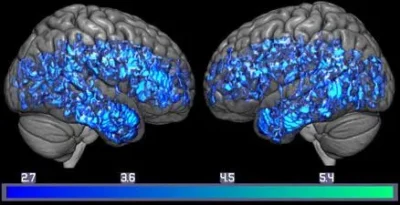

I ricercatori hanno scoperto che i pazienti con MCI avevano livelli più bassi del trasportatore della serotonina e livelli più alti di Aβ rispetto ai controlli sani. I pazienti con MCI avevano livelli di trasportatore della serotonina fino al 25% più bassi nelle regioni corticali e limbiche rispetto ai controlli sani. In particolare, i ricercatori riportano che livelli più bassi di trasportatore della serotonina sono stati trovati nelle regioni corticali, limbiche e sottocorticali del cervello in quelli con MCI, aree specificamente responsabili della funzione esecutiva, delle emozioni e della memoria.